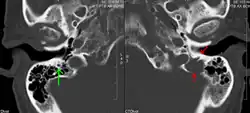

The diagnostic examination of a person with suspected multiple myeloma typically includes a skeletal survey. This is a series of X-rays of the skull, axial skeleton, and proximal long bones. Myeloma activity sometimes appears as "lytic lesions" (with local disappearance of normal bone due to resorption) or as "punched-out lesions" on the skull X-ray ("raindrop skull"). Lesions may also be sclerotic, which is seen as radiodense.[76] Overall, the radiodensity of myeloma is between −30 and 120 Hounsfield units (HU).[77] Magnetic resonance imaging is more sensitive than simple X-rays in the detection of lytic lesions. An MRI may supersede a skeletal survey, especially when vertebral disease is suspected. Occasionally, a CT scan is performed to measure the size of soft-tissue plasmacytomas. Nuclear Medicine Bone scans are typically not of any additional value in the workup of people with myeloma (no new bone formation; lytic lesions not well visualized on nuclear bone scan).

A CT of the brain revealed a lytic lesion in the left temporal bone (right side of image), and petrous temporal bones involving the mastoid segment of the facial nerve canal. Red arrows: lesion; green arrow: normal contralateral facial nerve canal. The lesions are consistent with a myeloma deposit.